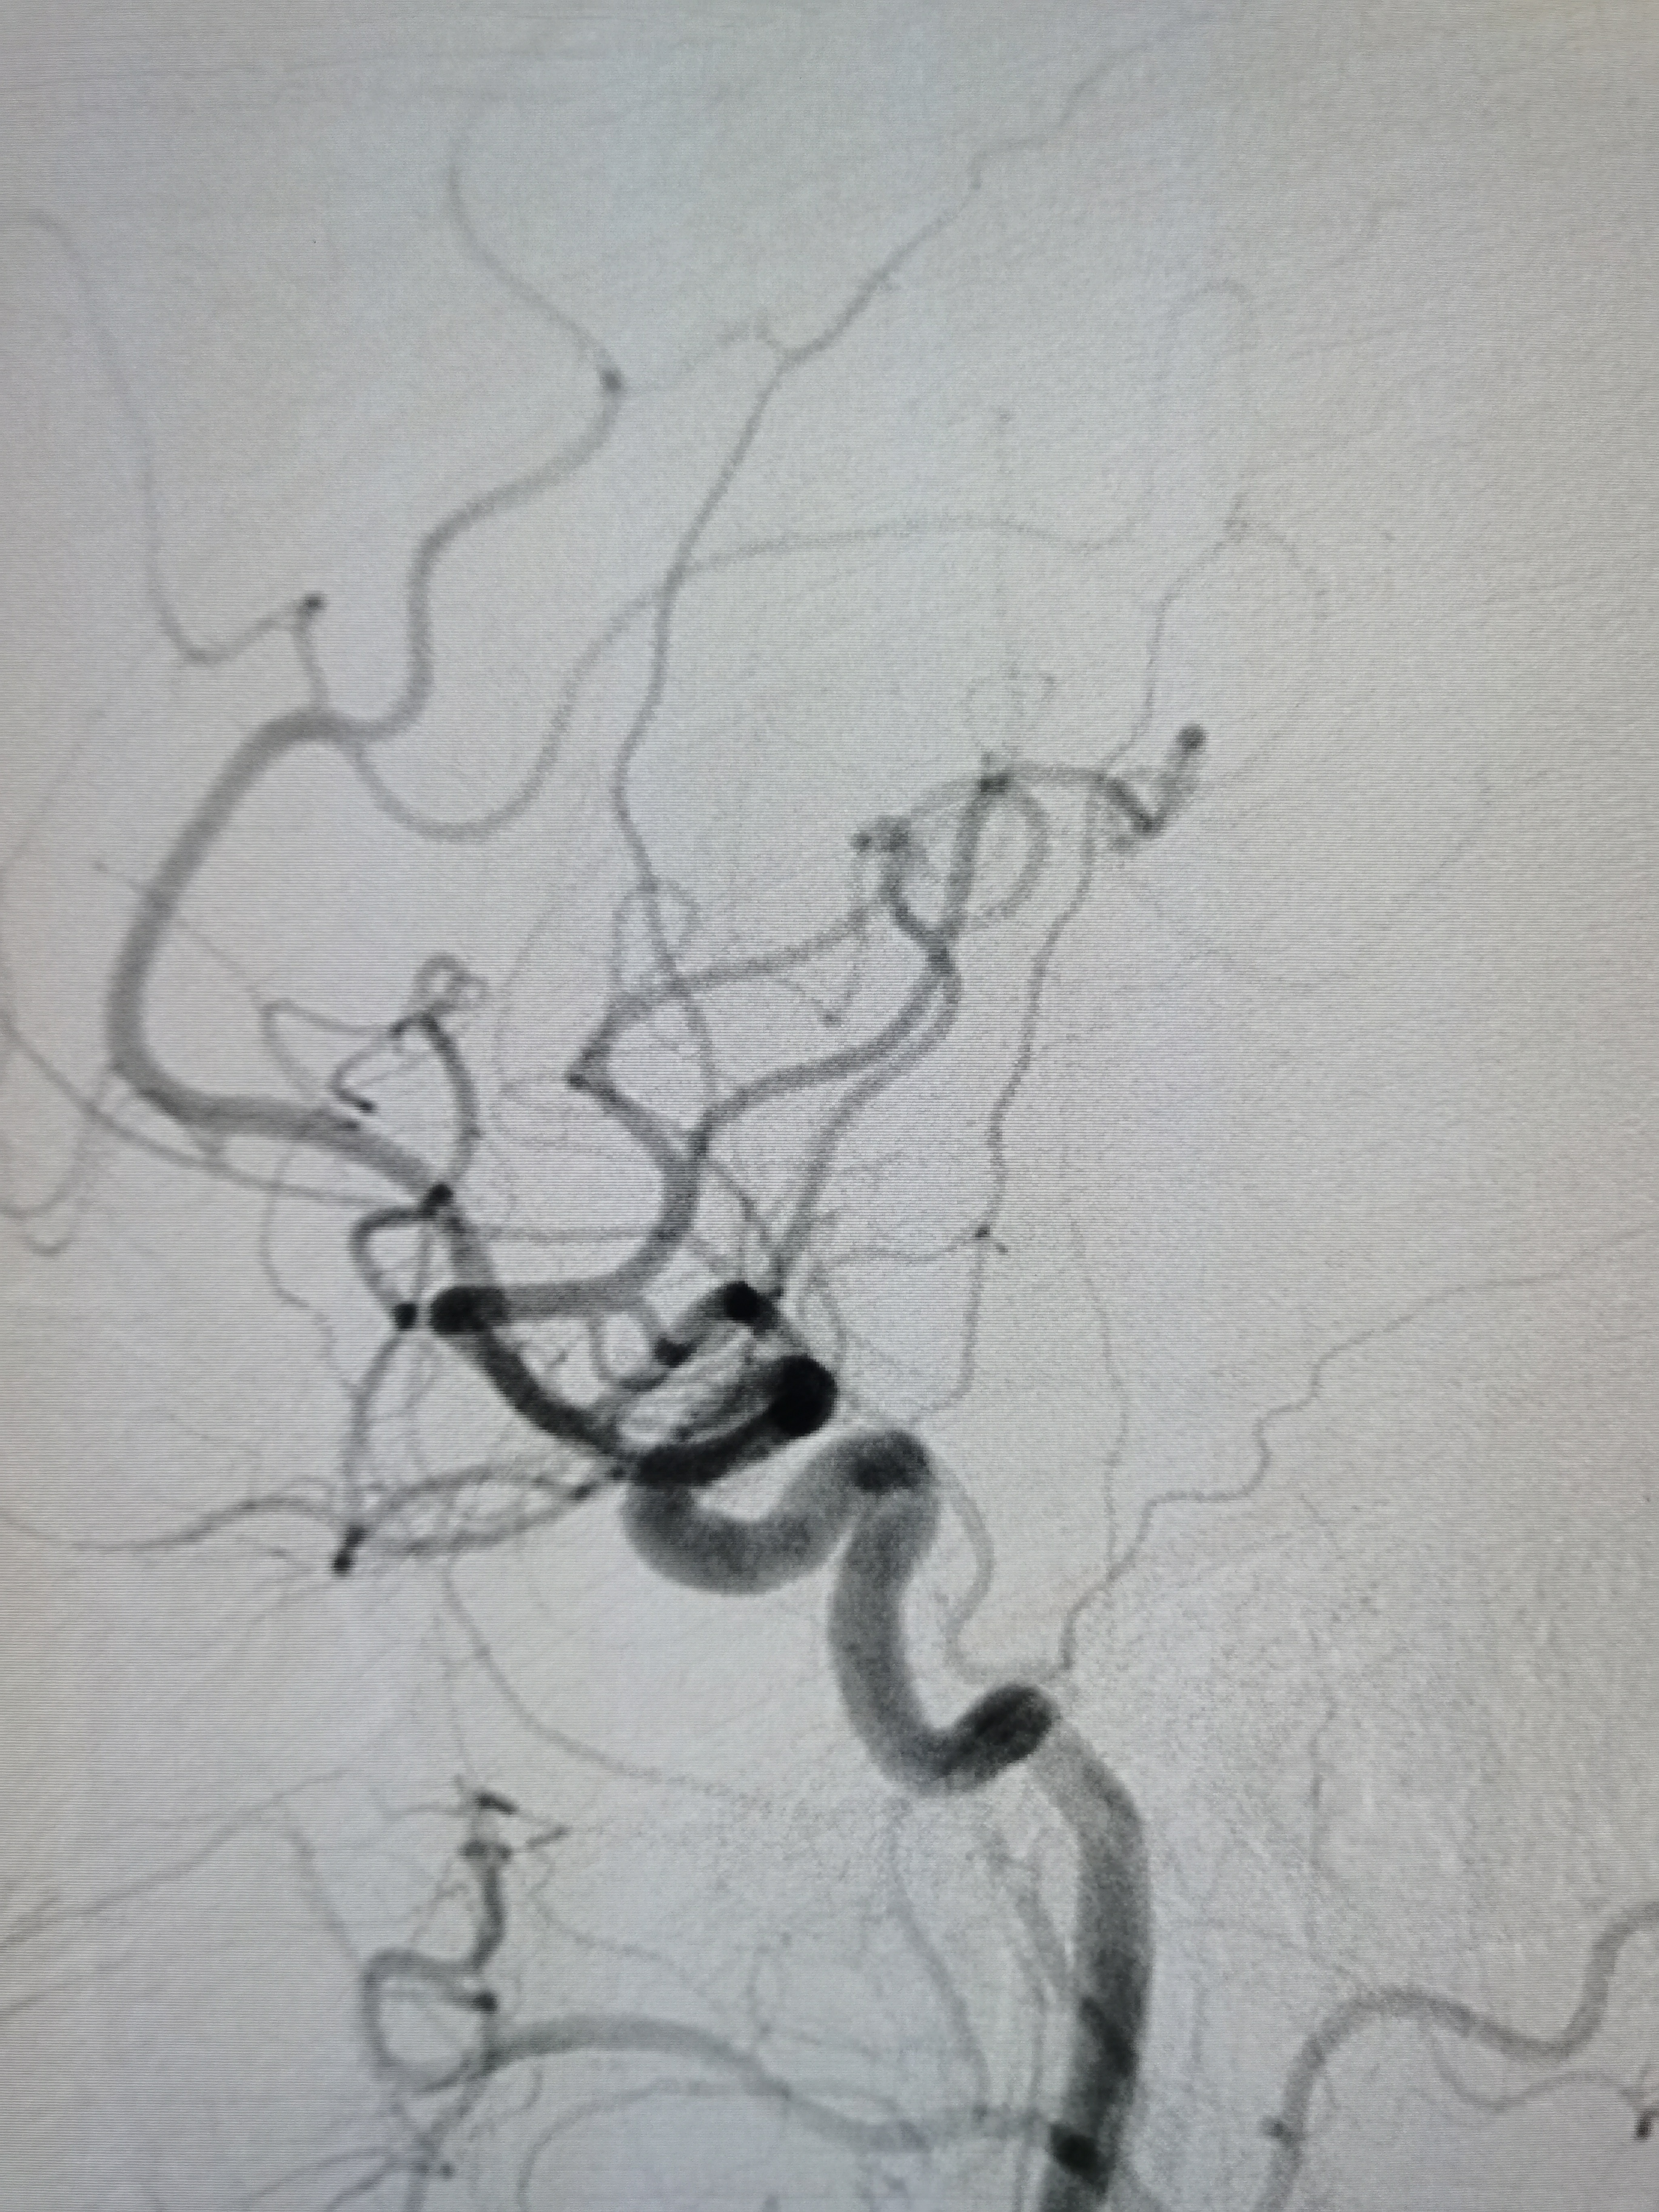

将8F导引导管送至左侧锁骨下动脉近左椎动脉起始部,微导丝顺利通过病变,2.0/20球囊预扩病变。

2、CTA证实左椎动脉起始部重度狭窄合并血栓,系责任血管,存在急性闭塞或残存血栓脱落至基底动脉风险,需积极处理。

3、手术过程中,先用小球囊扩张病变,观察血栓情况,及时应用支架全程覆盖血栓及病变部位,成形满意。